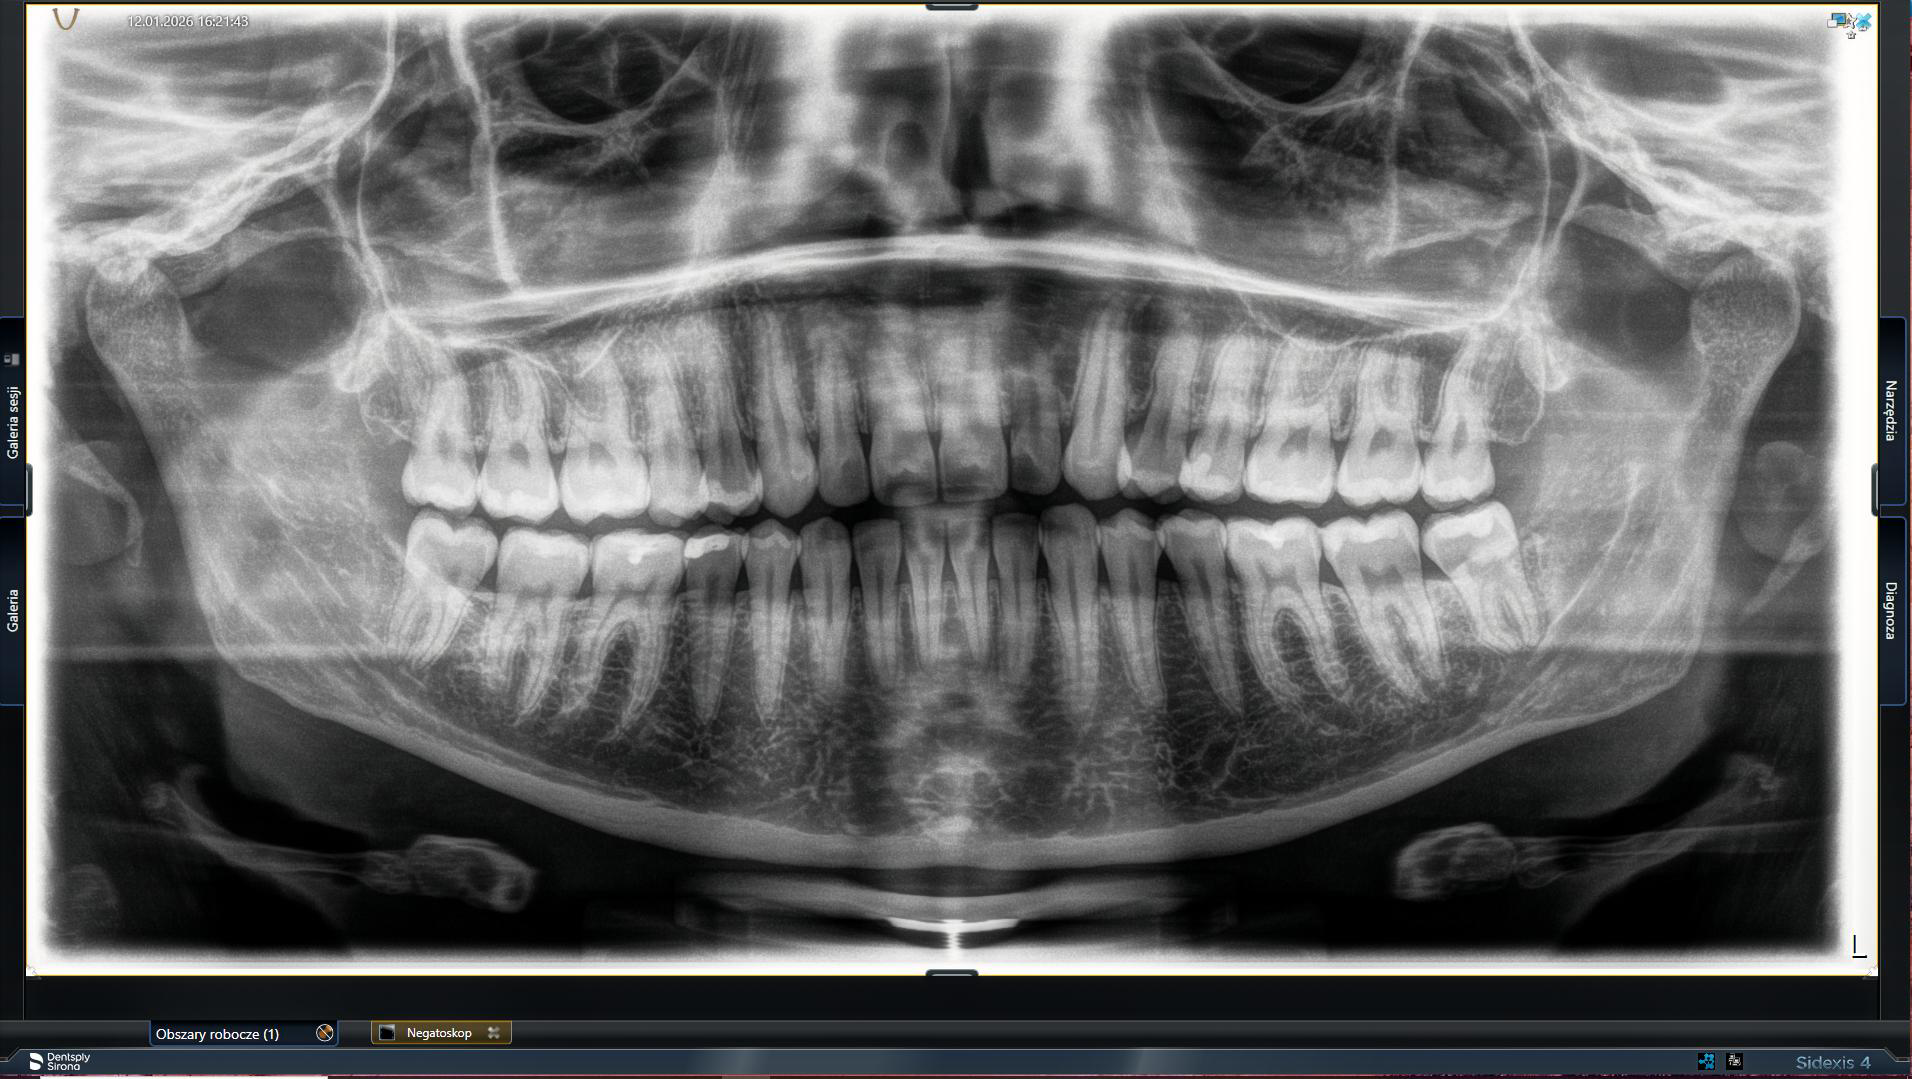

Zdjęcie panoramiczne (pantomograficzne) – całościowy obraz uzębienia

Zdjęcie pantomograficzne, często nazywane również zdjęciem panoramicznym zębów, to podstawowe badanie przeglądowe. Na jednym zdjęciu uzyskujemy pełen obraz wszystkich zębów (zarówno tych widocznych, jak i zatrzymanych), kości szczęki i żuchwy, stawów skroniowo-żuchwowych oraz zatok szczękowych. Jest to idealne narzędzie do oceny ogólnego stanu zdrowia jamy ustnej i stanowi punkt wyjścia do planowania większości kompleksowych terapii. Jeśli szukasz miejsca, gdzie można wykonaćpantomogram zębów we Wrocławiu, nasza klinika oferuje to badanie na miejscu.